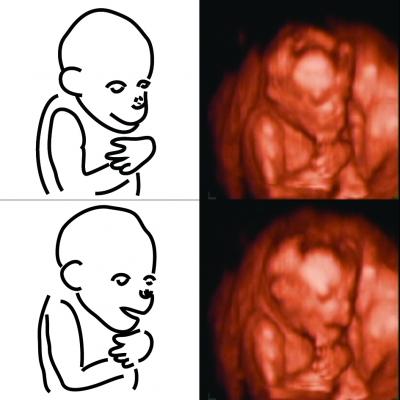

Humans' superior brain size in comparison to their chimpanzee cousins traces all the way back to the womb. That's according to a study reported in the September 25 issue of Current Biology , a Cell Press publication, that is the first to track and compare brain growth in chimpanzee and human fetuses.

Hirata and colleagues Tomoko Sakai and Hideko Takeshita now find that human and chimp brains begin to show remarkable differences very early in life. In both primate species, the brain grows increasingly fast in the womb initially. After 22 weeks of gestation, brain growth in chimpanzees starts to level off, while that of humans continues to accelerate for another two months or more. (Human gestation time is only slightly longer than that of chimpanzees, 38 weeks versus 33 or 34 weeks.)

The findings are based on 3D ultrasound imaging of two pregnant chimpanzees from approximately 14 to 34 weeks of gestation and comparison of those fetal images to those of human fetuses. While early brain differences were suspected, no one had previously measured the volume of chimpanzee brains as they develop in the womb until now.